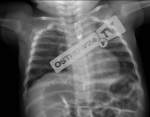

Lekarka, której dotyczy sprawa jest mieszkanką Ostrowa Wlkp. Często zmieniała miejsca pracy. W tamtym okresie pracowała w szpitalu powiatowym w Krotoszynie. Na Szpitalny Oddział Ratunkowy zgłosili się rodzice z informacją, że ich 6-miesięczny syn Kubuś połknął agrafki. Wcześniej wyrwał ją z medaliku przyczepionego we wózku. Lekarka zleciła wykonanie badań, w tym także prześwietlenia RTG.